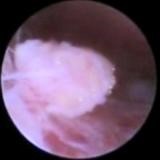

Рис. Свободно флотирующее в суставе тело

Первым этапом осматривается полость сустава, обнаруживаются патологические изменения в нём, после этого под визуальным контролем устраняются выявленные нарушения, а именно, рассекаются сайки, высвобождается суставной диск, удаляются флотирующие фрагменты тканей или сформировавшиеся кальцинированные тела. Если имеется воспалительная инфильтрация тканей, то эта зона коагулируется, что дает хороший противовоспалительный эффект. При необходимости может быть надсечено сухожилие латеральной крыловидной мышцы, и с помощью электро- или лазерной коагуляции обрабатываются связки биламинарной зоны. Это делается для уменьшения силы тяги мышцы и уплотнения связок, возвращающих диск в исходное положение.

Рис. Внутрисуставные спайки

В ряде случаев производится фиксация диска к суставной головке нижней челюсти с помощью специальных рассасывающихся винтов и пинов, или прошивание диска. Идея этих манипуляций состоит в удержании диска и предупреждении его избыточных смещений, но, имеющийся мировой опыт на этот счет неоднозначен. Завершается операция обильными промываниями сустава и введением специальных препаратов, улучшающих скольжение суставных элементов, ускоряющих рост и восстановление хрящевой ткани.